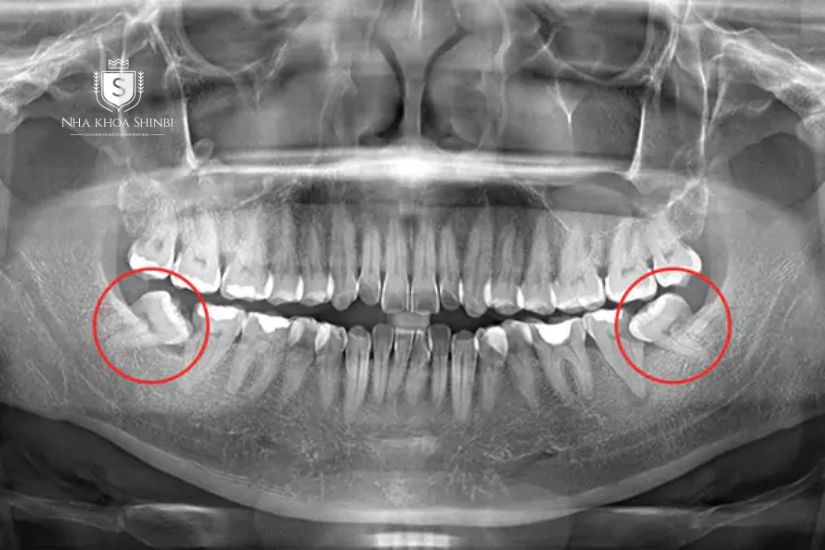

Trường hợp răng số 7 mọc thẳng và không gặp bất kỳ vấn đề nào, việc nhổ sẽ diễn ra nhanh chóng và chi phí thường thấp. Tuy nhiên, nếu răng bị mọc lệch, ngầm hoặc đâm vào răng số 6, quy trình nhổ sẽ phức tạp hơn, yêu cầu kỹ thuật cao hơn, dẫn đến tăng chi phí.

Răng số 7 mọc lệch khi chụp X-quang răng

Ngoài ra, nếu răng số 7 đã bị sâu nặng, vỡ lớn, hoặc viêm nhiễm (như áp xe), bác sĩ cần tiến hành xử lý và kiểm soát nhiễm trùng trước khi nhổ. Điều này cũng làm tăng thêm thời gian và chi phí điều trị. Đối với những răng từng trải qua điều trị tủy hoặc có vật liệu nha khoa bên trong (như trụ kim loại khi trồng răng implant), việc nhổ cũng trở nên khó khăn hơn, đòi hỏi kinh nghiệm và kỹ thuật cao hơn từ bác sĩ.